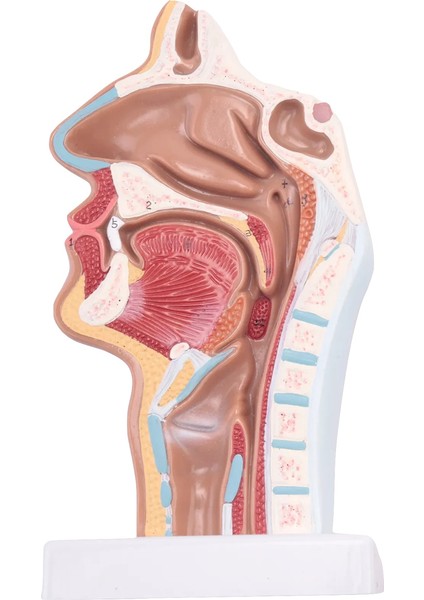

Insan Anatomik Nazal Boşluk Boğaz Anatomi Modeli Bilim Sınıfı Çalışma Ekran Öğretim Modeli (Yurt Dışından)

Bu model, ağız, burun, farinks ve larinks iç yapısını ve serebrovasküler ve kranial sinirler gibi yapıları gösterir. (dijital işaretle)Ürün özellikleri